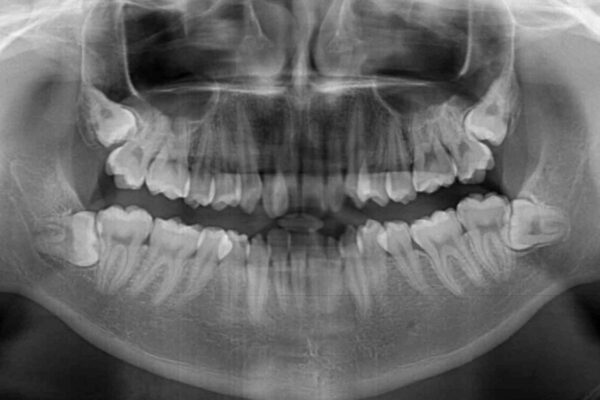

治療前

• 全顎的なクロスバイト 補助装置を用いてワイヤー矯正 治療前画像

前歯のクロスバイトや八重歯の他に、左右最後臼歯のシザーズバイト(鋏状咬合)が認められました。

シザーズバイト改善のために補助装置を使用しながら、ワイヤー装置にて全体の歯列を整えることとしました。